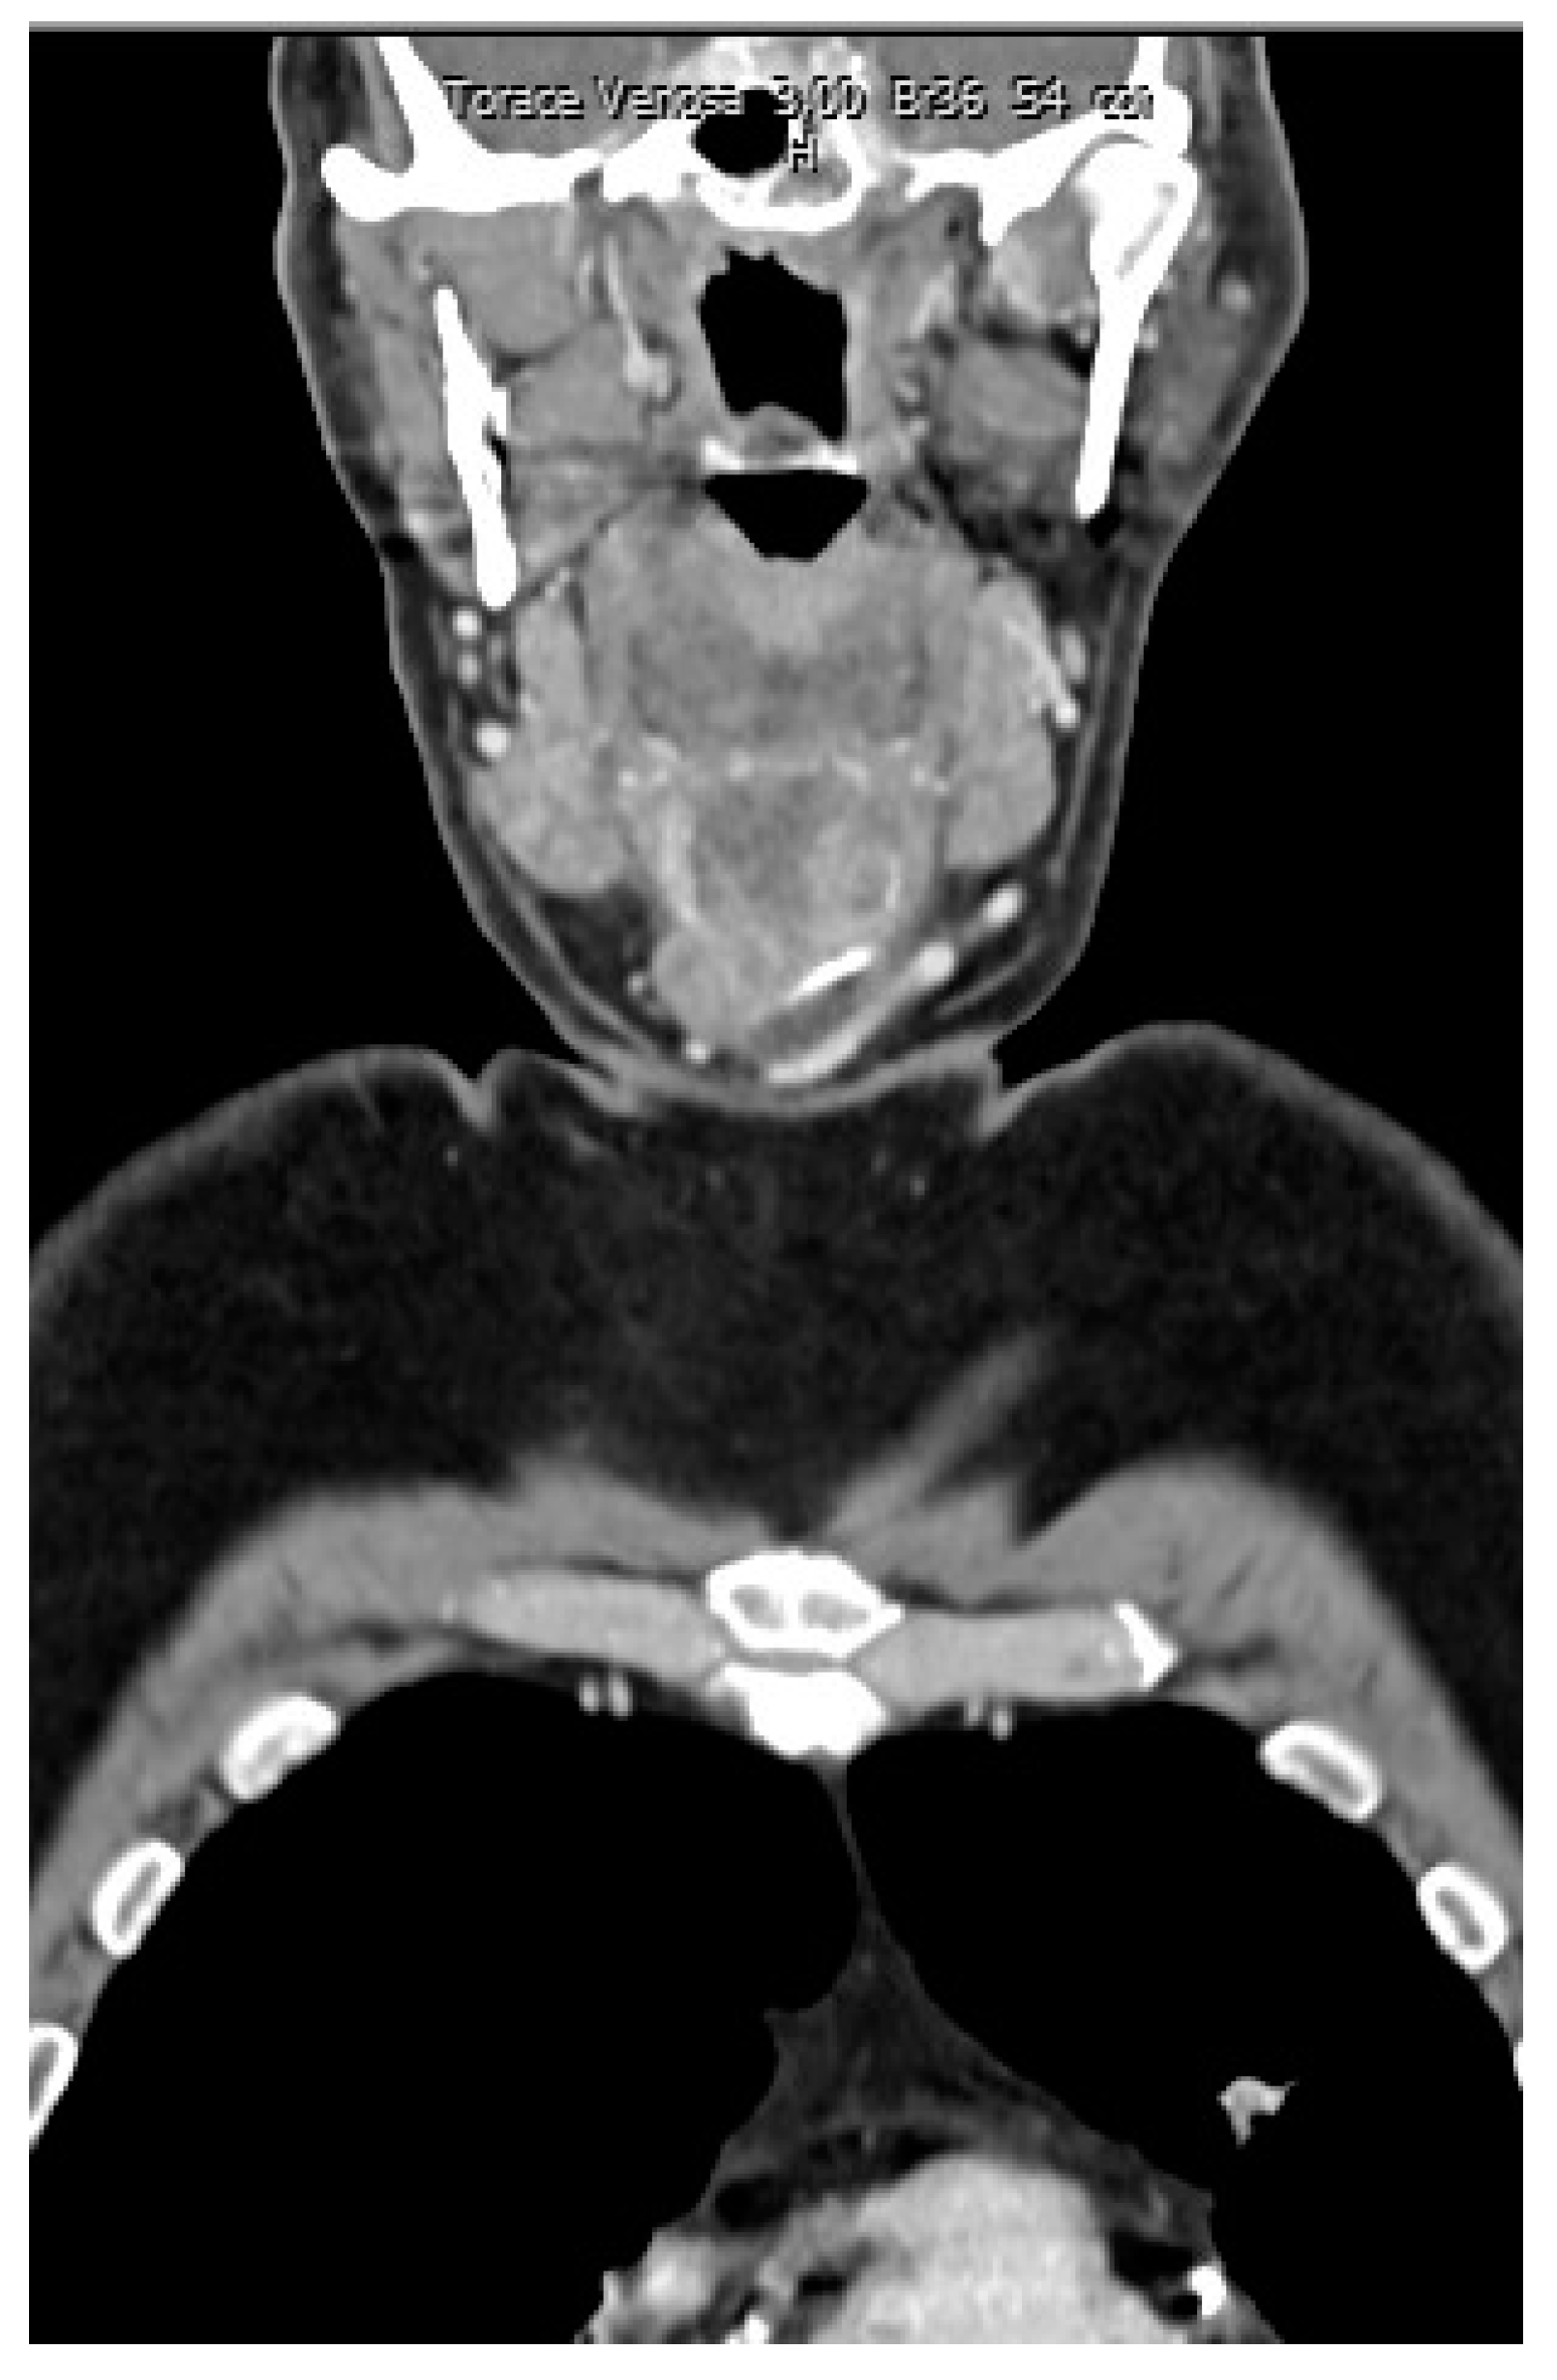

A rounded osteolytic mass of 4.5 × 3.6 cm in size in the central part of the hyoid bone was evident from a contrast-enhanced computed tomography (CT).

CT demonstrated massive osteolysis and cortical destruction with the enlargement of the body of the hyoid bone. The osteolytic mass of the hyoid bone showed a slight soft tissue extension toward the pre-epiglottic region. An evident extension towards pre-hyoid muscles was also noted. The lumen of the airways was not affected, and no pathological changes were evident in the surrounding structures of the neck (Figure 1, Figure 2 and Figure 3).

Figure 1. Contrast-enhanced computed tomography (CT) showed a rounded osteolytic mass of 4.5 × 3.6 cm in size in the central part of the hyoid bone: coronal view.